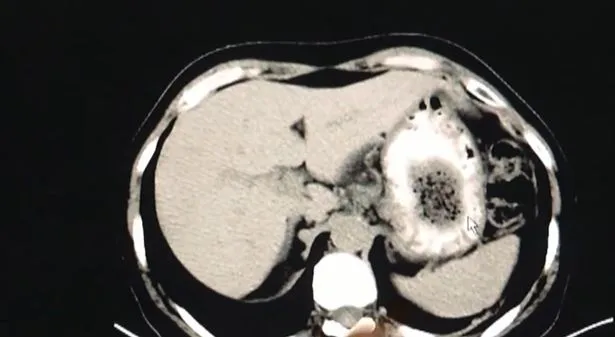

ด้านหมอจู้เจิน ผู้เชี่ยวชาญด้านระบบทางเดินอาหารประจำโรงพยาบาล เปิดเผยว่า ผลการสแกนแสดงให้เห็นเงาในท้องของนางจาง แต่มันก็ยากที่จะระบุและอาจเป็นอะไรก็ได้ตั้งแต่ถุงอากาศไปจนถึงเนื้องอก

อย่างไรก็ตามเมื่อหมอได้ทำการส่องกล้องตรวจภายในท้องก็พบว่ามีก้อนสิ่งแปลกปลอมขนาด 2 นิ้วอยู่ในกระเพาะอาหารของเธอ และนั่นทำให้เกิดอาการรู้สึกไม่สบายเนื่องจากสิ่งแปลกปลอมนี้มีขนาดที่ค่อนข้างใหญ่

ด้านนางสาวจางได้เปิดเผยว่า เธอเป็นคนที่ชอบกินเนื้อปูและลูกพลับมาก เธอคิดว่าสิ่งนี้อาจเป็นสาเหตุของอาการเจ็บป่วยดังกล่าว ด้วยเหตุนี้นางสาวจางจึงต้องเข้ารับการรักษาด้วยคลื่นอัลตร้าซาวด์เพื่อทำลายสิ่งคล้ายก้อนหินในกระเพาะอาหารของเธอ

ขณะเดียวกันหมอจู้ได้กล่าวว่า “สำหรับผู้ป่วยที่ระบบย่อยอาหารอ่อนแออยู่แล้ว การกินลูกพลับและปูจำนวนมากในช่วงเวลาสั้น ๆ สามารถนำไปสู่การก่อตัวของ bezoar เนื่องจากโปรตีนและกรดแทนนิน”